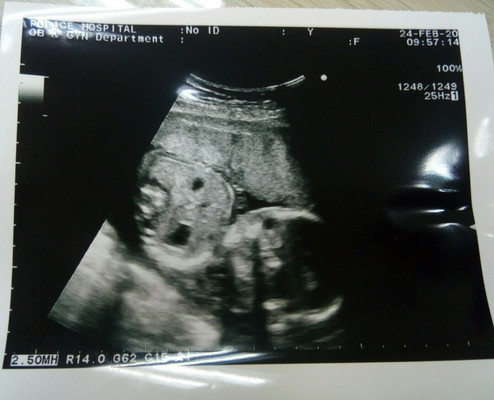

คุนหมอบอกกับคุนแม่ว่า ' ลูกสาว ' คะ แม่กลัวไม่ชัวร์ เลยโพสรูปนี้สอบถามคุนแม่ท่านอื่นดูคะ ตอนนี้อายุครรภ์ได้ 22 สัปดาห์ 5 วัน คงเห็นชัดแล้วใช่ไมคะ ขอบคุนทุกคอมเม้นคะ

มุมนี้มองไม่เห็นเพศนะคะ คุณแม่ถามหมอดีกว่าค่ะ

ภาพนี้ไม่บอกเพศนะจ๊ะ มุมนี้ดูเพศไม่ได้จ้า

น่าจะผู้หญิงนะคะ จากภาพคล้ายๆกันอยู่

มุมนี้ไม่เห็นเพศค่ะแม่

มุมนี้ไม่บอกเพศนะแม่

ไม่เห็นเพศค่ะ